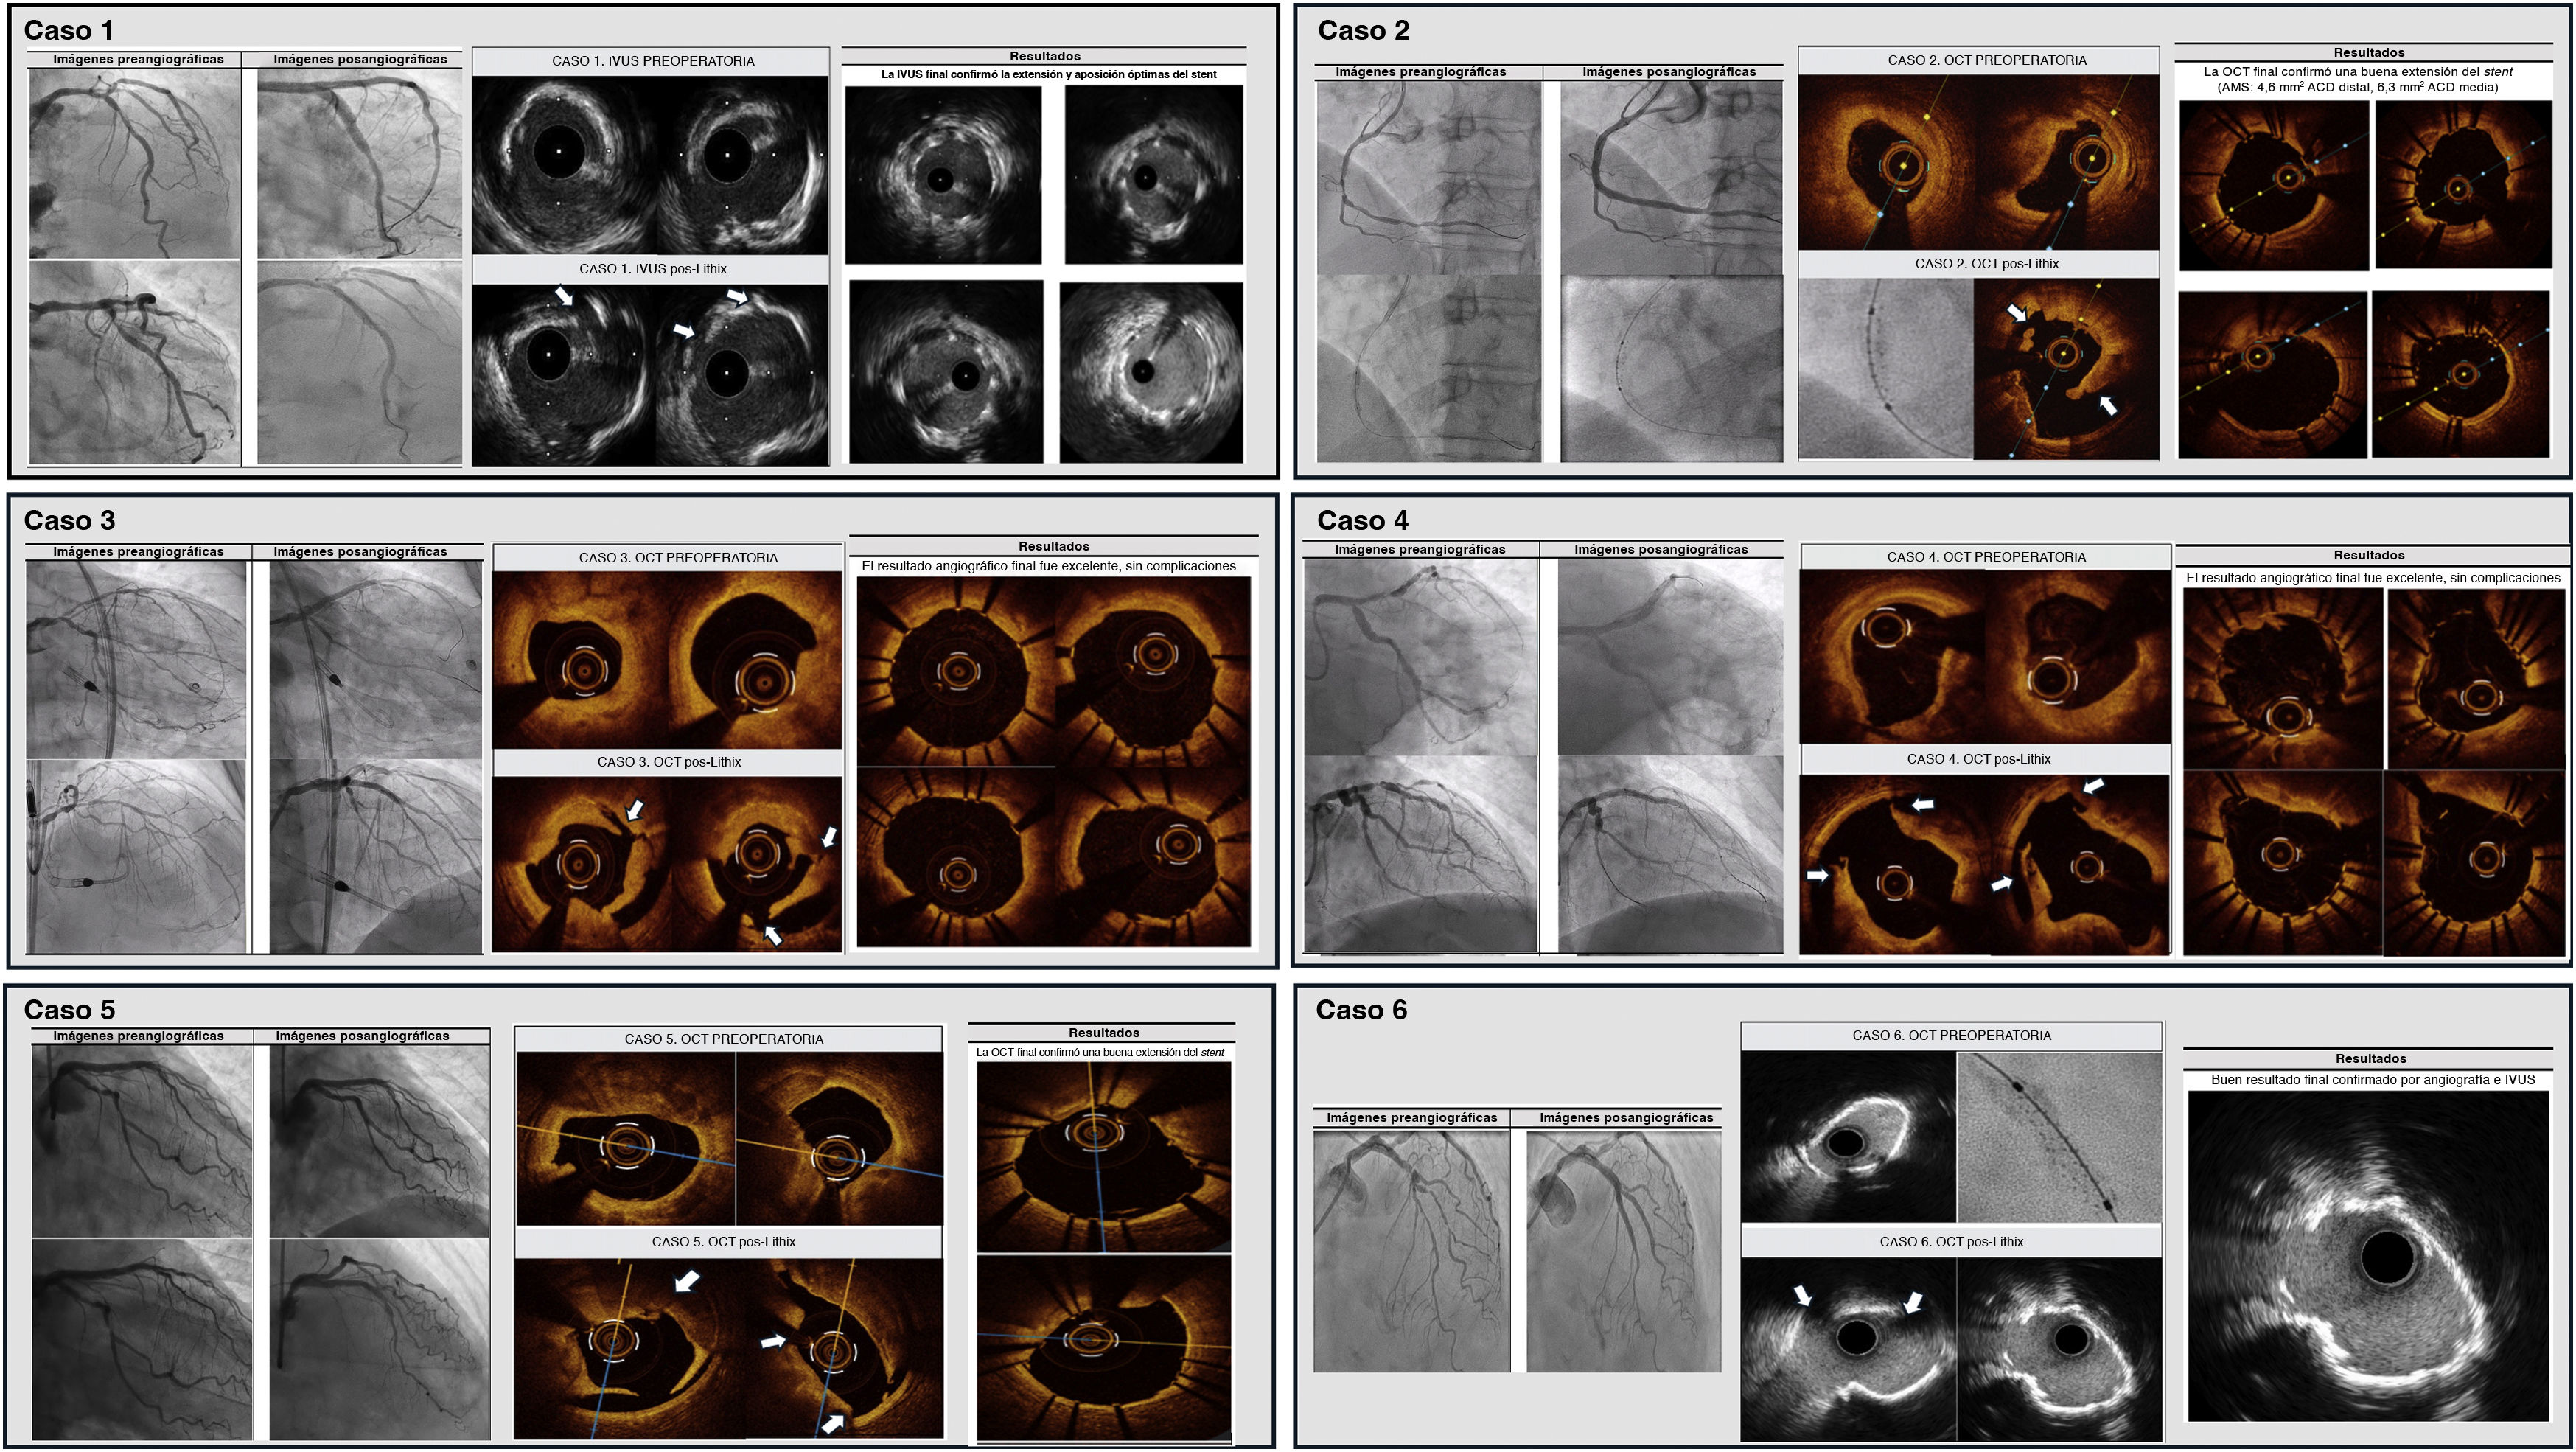

Todos los pacientes presentaban lesiones coronarias gravemente calcificadas, incluyendo bifurcaciones, enfermedad del tronco común izquierdo y daño difuso de numerosos vasos (tabla 1). El aparato LithiX se empleó como una estrategia principal de modificación de la placa, ya fuera desde el principio, ya tras el fracaso de la preparación convencional de la lesión. En todos los casos, el uso del balón LithiX dio como resultado una preparación eficaz de la lesión, según confirmaron las imágenes angiográficas e intracoronarias. La tomografía de coherencia óptica (OCT) o la ecografía intravascular (IVUS) demostró de forma sistemática la fractura del calcio (figura 1), con rotura visible de las capas calcificadas profundas, agrandamiento luminal y expansión optimizada del stent. No se comunicaron complicaciones relacionadas con el sistema LithiX. El implante del stent fue satisfactorio en todos los pacientes, con resultados angiográficos finales óptimos. Los siguientes resúmenes de casos hacen hincapié en la relevancia clínica y el valor terapéutico del sistema LithiX IVL en una variedad de lesiones coronarias anatómicamente complejas y de gran riesgo. La tabla 1 presenta un resumen estructurado de las características clínicas, los retos anatómicos y las estrategias operatorias que implican el uso de LithiX para la modificación de la placa. Cada uno de los casos se guio por imágenes endovasculares (IVUS u OCT), con confirmación angiográfica, y verificación de la fractura del calcio y la expansión óptima del stent. La tabla también detalla los motivos específicos para el uso de LithiX, ya sea seleccionado como estrategia de primera línea en anatomías calcificadas complejas, ya como recurso de rescate tras el fracaso de las técnicas convencionales.

Imágenes endovasculares (IVUS y OCT) antes y después de utilizar el sistema LithiX en 6 casos clínicos. Las imágenes preoperatorias muestran placas calcificadas graves. Las imágenes posteriores a LithiX demuestran de forma sistemática fracturas de calcio visibles (flechas blancas), lo que indica una modificación eficaz de la placa. ACD: arteria coronaria derecha; AMS: área mínima del stent; IVUS: ecografía intravascular; OCT: tomografía de coherencia óptica.